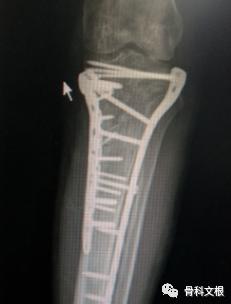

经过充分术前准备,手术团队施行“原内固定拆除+原骨折线截骨+干骺端外翻截骨复位”内固定治疗。仅仅1个多小时,手术顺利结束,术中出血50ml,术后经过康复治疗,刘先生对手术效果非常满意。

(矫正后)